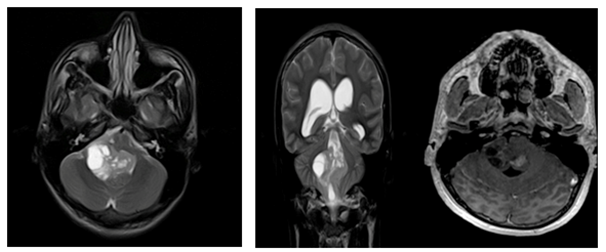

Case report no. 3

A 1-year-old male patient who consulted for swallowing disorder, sobbing spasm, he fell down and later presented torticollis, was taken to the emergency department, performed brain tomography and MRI that evidenced tumoral lesion in the posterior fossa that compromises left cerebellar hemisphere, which measures 2.8 * 1.6 cm, heterogeneous, with calcifications, enhances with contrast and compresses the brain stem deforming the IV ventricle; magnetic resonance imaging of the cervical spine did not show tumor spread (Figure 2b). Surgery was performed with incomplete resection of 70%. The post-surgical neurological state was a patient with hypoactivity, involvement of VII, IX, X, XI cranial pairs, swallowing disorder, left hemiparesis and cerebellar syndrome. The evolution was regular, the control resonance showed the surgical history and the presence of 2 residual oval lesions, the largest located near the IV ventricle, with compression of the cerebral stem and the second located in the cerebellar hemisphere. The second surgical intervention was performed, infiltrating lesions were observed in the IV ventricle and Lushka foramen, complete resection was achieved. The pathological diagnosis was recurrent ependymoma, with findings of monomorphic cells of round and oval hyperchromatic nuclei, forming perivascular pseudorosettes, frequent mitosis and necrosis compatible with anaplastic ependymoma (Figure 1).

Figure 2b Radiology: Anaplastic Ependymomas.

b. Patient No.3. Pre-surgical and post-surgical axial T2 sequences, a tumor presenting calcifications, adjacent to the fourth ventricle, the uptake is heterogeneous with annular predominance. In the post-surgical control brain resonance, a residual lesion is observed, with persistent uptake of annular predominance.